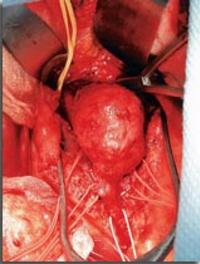

Depuis la publication princeps de Charles Dubost en 1951, on peut traiter chirurgicalement les anévrysmes de l’aorte abdominale (AAA). [...]

Depuis maintenant plus d’une décennie, des techniques de réparation endovasculaire (REV) de l’aorte ont été mises au point pour le [...]